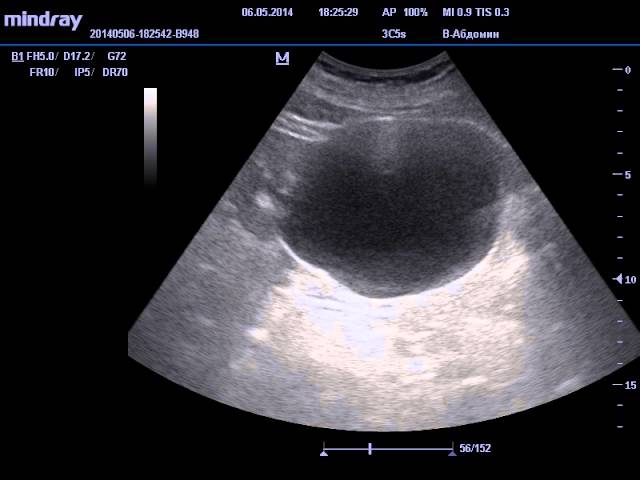

На видео изображен орган, у которого показатели в норме: